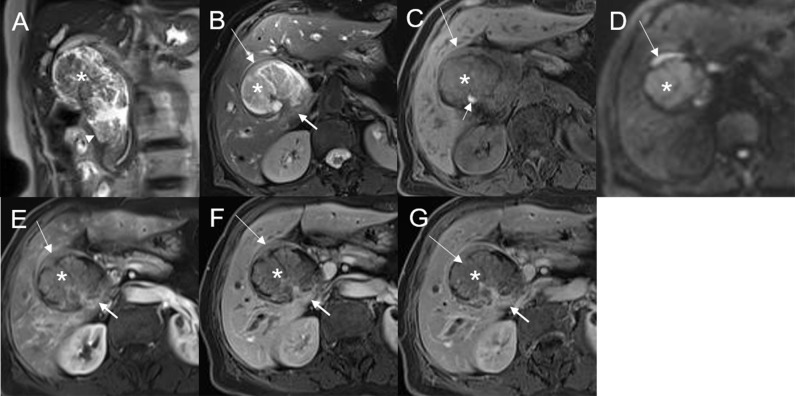

The 28 patients had a total of 32 lesions; while 26 patients had single lesions, 2 patients had three lesions each (one patient had dual plaque-like masses and an infiltrative mass, and the other patient had three plaque-like masses; f2).

Mean lesion size in the whole sample was 30.83 ± 20.93 mm. All patients presented with an intraluminal ductal mass. While 14/32 (43.75%) lesions presented morphologically as focal eccentric-type masses (f3), 9/32 (28.13%) presented as plaque-like masses, 4/32 (12.50%) as bile duct casting masses, and 5/32 (15.62%) as infiltrative masses. In addition, 8/32 (21.88%) lesions showed a frond-like superficial appearance accompanied by other morphologically categorized appearances other than plaque-like superficial (f4, f5; T2).

On standard MRI scanning, 24/32 (75%) lesions showed hyperintensity and 9/32 (25%) showed isointensity on T2WI, while 9/32 (28.12%) lesions showed isointensity and 23/32 (71.88%) showed hyperintensity on T1WI. In addition, 3/32 (9.38%) lesions showed speckled hyperintensity on T1WI (f7).

On dynamic enhanced MRI, 14/18 (77.78%) lesions showed moderate enhancement, 2/18 (11.11%) showed obvious enhancement, and 2/18 (11.11%) showed slight enhancement. While 13/18 (72.22%) lesions showed stable and persistent enhancement, 5/18 (27.78%) showed wash-in and wash-out enhancement (T2).

On DWI (b = 800 s·mm-2), 5/32 (15.63%) adenomas showed isointensity (f2) and 27/32 (84.37%) showed hyperintensity. In 2/32 (6.25%) cases, the bile duct wall around the lesion showed hyperintensity on DWI (f8). The mean ADC value of the lesions was 1.65 ± 0.38 × 10-3 mm2·s-1 (T2).